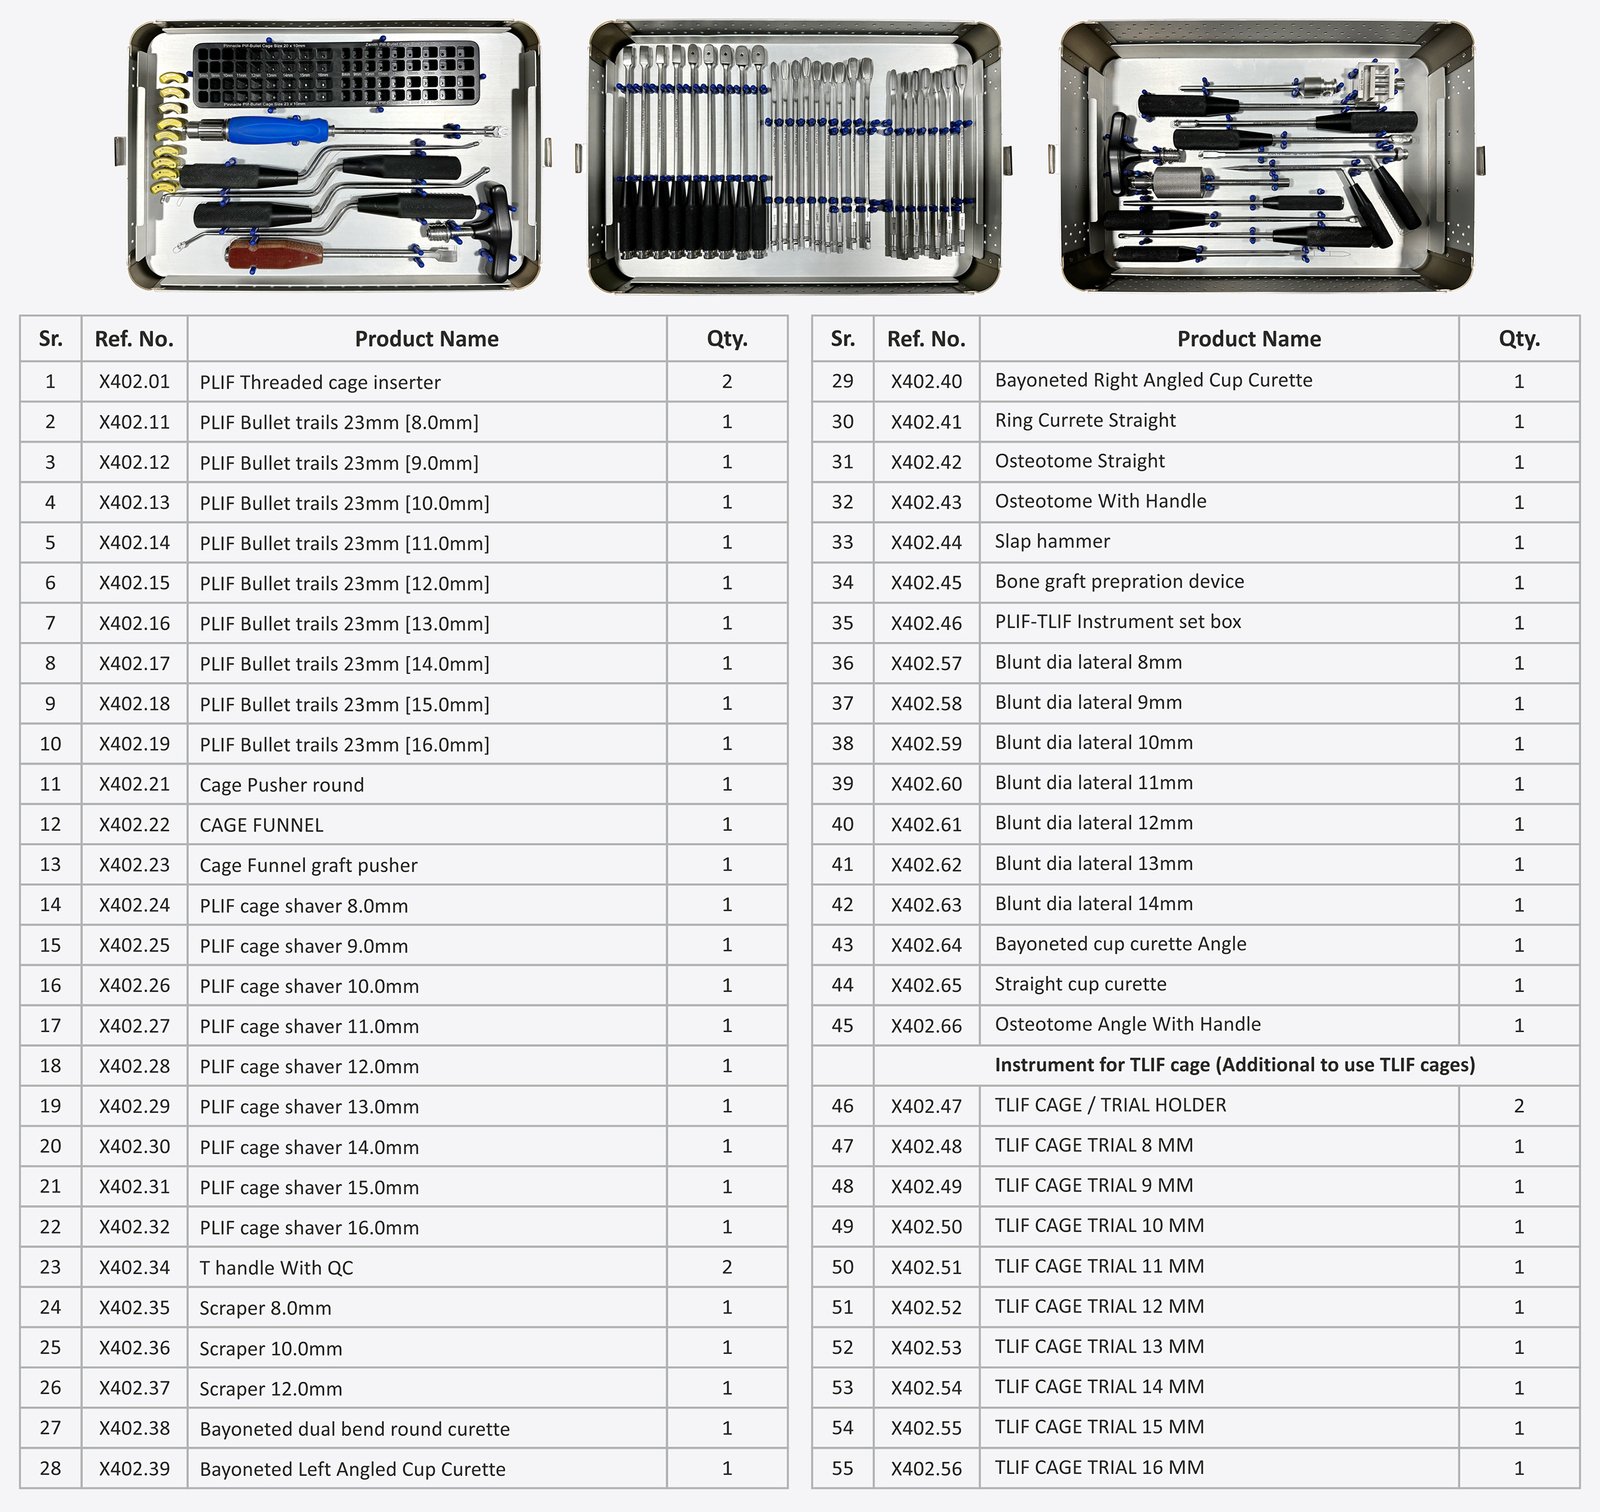

The Zenith PLIF Bullet Cage is a cutting-edge interbody fusion device designed for Posterior Lumbar Interbody Fusion (PLIF) procedures. Engineered to provide optimal anatomical fit and support spinal stability, this bullet-shaped cage facilitates safe insertion and superior bone integration, making it a preferred choice among spine surgeons.

Length 20mm

Size : 20 x 10 x 7mm,4° to 20 x 10 x 16mm,4° (1mm Variation)

Length 23mm

Size : 23 x 10 x 7mm,4° to 23 x 10 x 16mm,4° (1mm Variation)

Length 26mm

Size : 26 x 10 x 7mm,4° to 26 x 10 x 16mm,4° (1mm Variation)

The TLIF Banana Cage, available in a hybrid combination of Titanium and PEEK, is a premium interbody device specifically designed for Transforaminal Lumbar Interbody Fusion (TLIF) procedures. Shaped to match the natural curvature of the spine, this banana-shaped cage ensures anatomical placement, maximum endplate contact, and enhanced fusion stability.

Ø 8.0mm to Ø 14mm (1 mm Variation)

Size : L(mm) 27 W(mm)12

L(mm) 30 W(mm)12